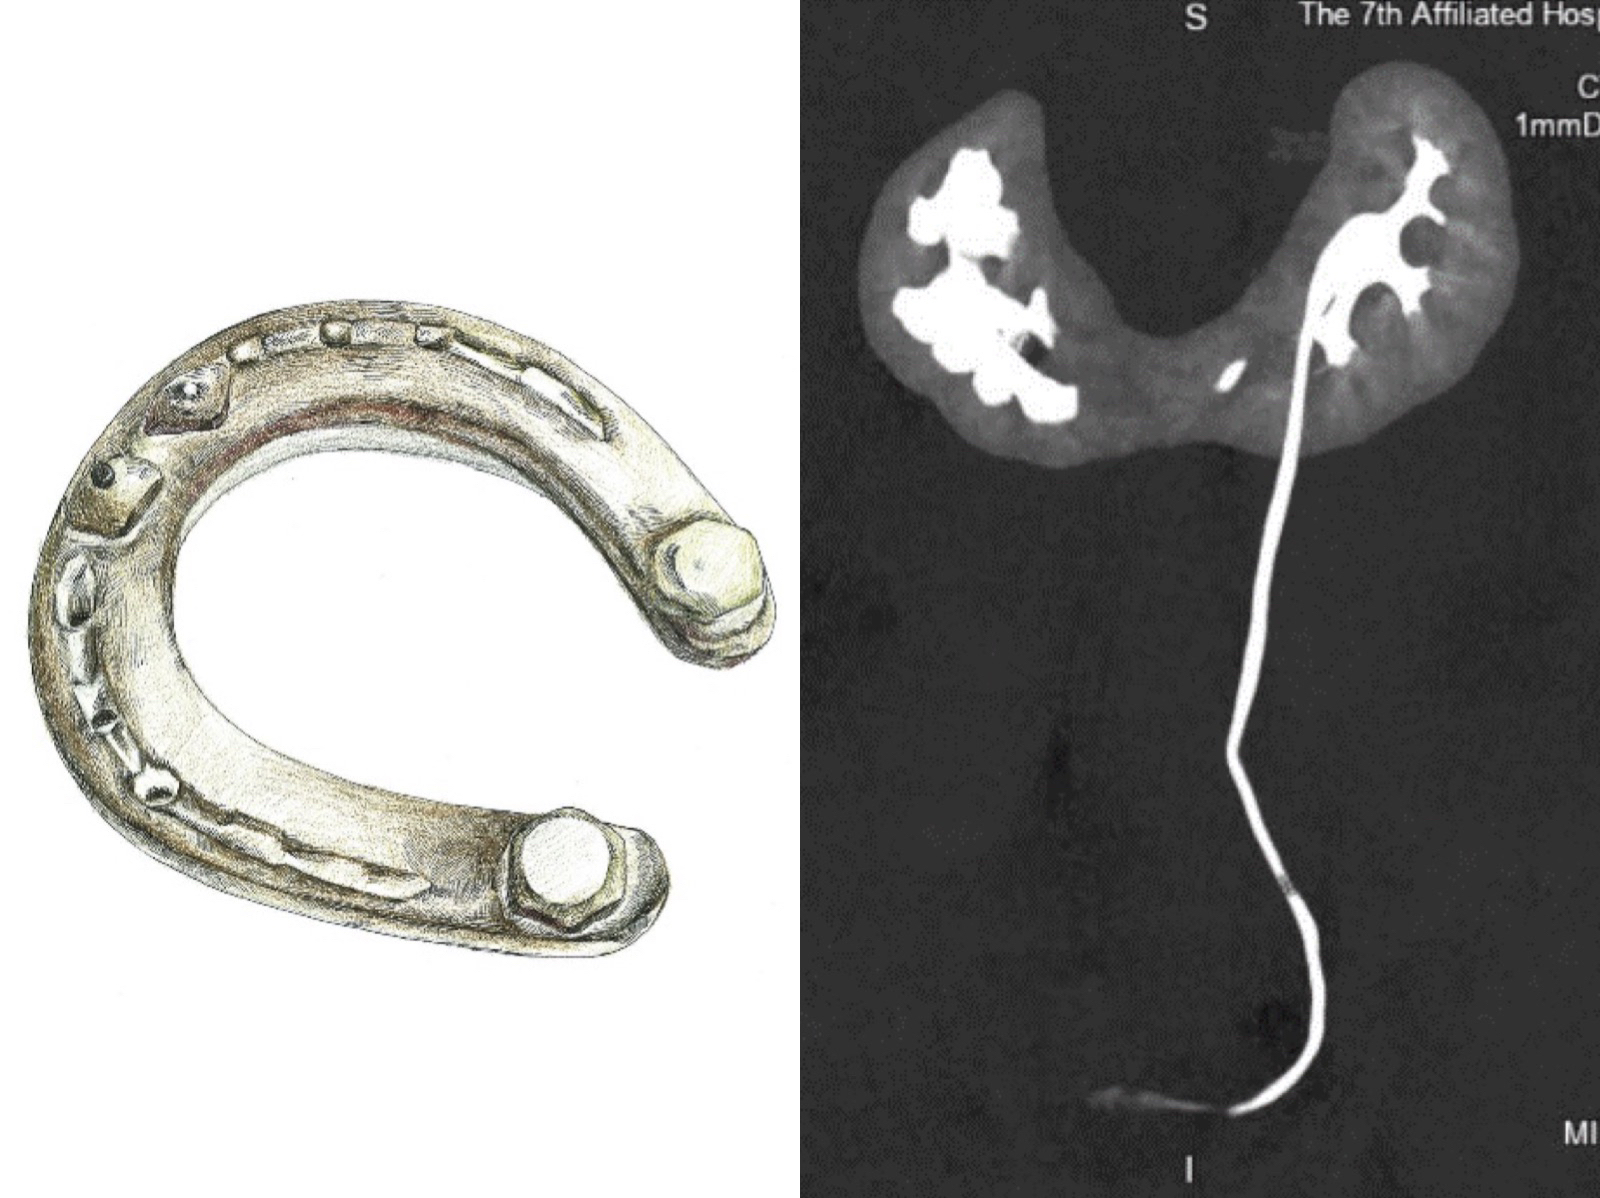

让他没想到的是,在中山大学附属第七医院泌尿外科,他还被检查出原本一左一右,独立的两个肾脏连在了一起,如同连体婴儿,被称为“马蹄肾”。

近日,马先生特地驱车到深圳的中山大学附属第七医院治疗肾结石。入院后完善检查发现,他的右肾多发结石范围达到了5.39cm。而且,他的两肾还很奇特,是非常罕见的“马蹄肾”。

马蹄肾是一种肾融合畸形,指两侧肾脏在中线通过肾实质或纤维组织形成的峡部相连,相连的部位多为下极。通俗来讲就是明明是一左一右两个肾,如今成了一对“连体肾”。

与正常人的肾脏相比,马蹄肾的位置比较深,并伴旋转畸形,所以穿刺比较困难。但是,在泌尿外科医护人员的精心准备下,最终在X光引导下顺利穿刺至肾盂,采用单通道钬激光碎石的方法将马先生的结石完整去除,手术过程十分顺利。